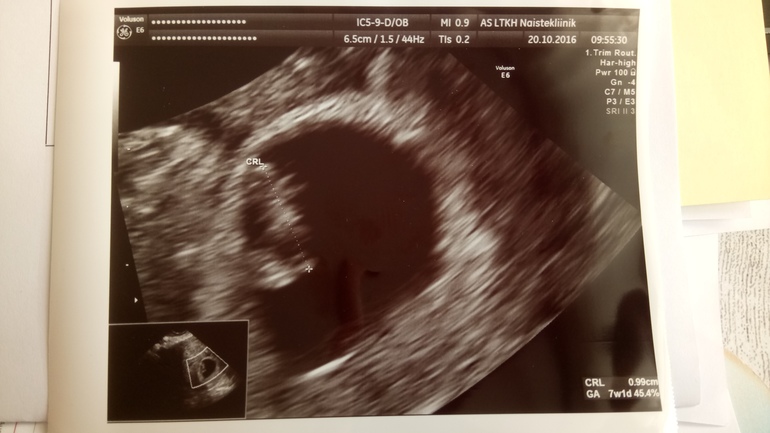

Сегодня мне официально подтвердили беременность !!! Нам подтвердили.

Срок поставили по узи 7 недель и 1 день и самое главное СЕРДЦЕБИЕНИЕ ЕСТЬ!!!